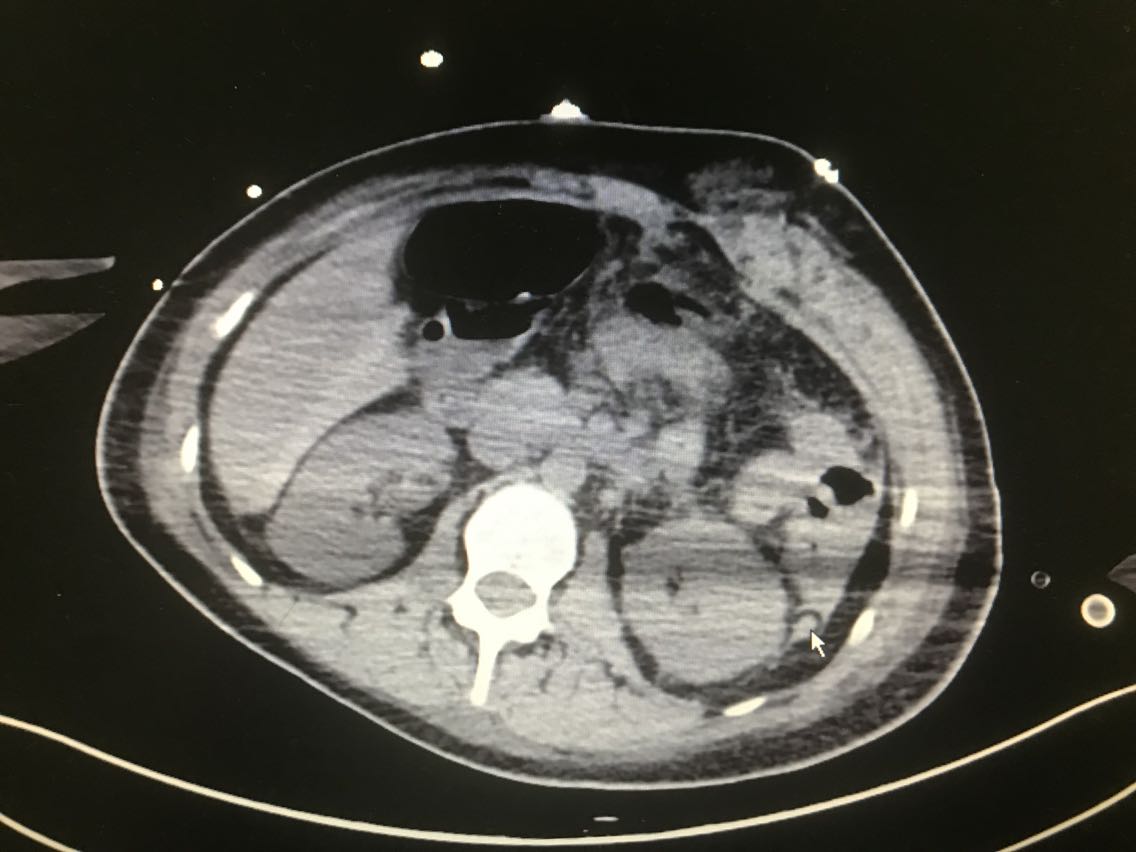

患者女性,31岁。 主诉:体检彩超发现左上腹异常回声10天 现病史:入院前10天,患者当地医院体检时彩超发现左上腹异常不均质稍低回声区,患者无胸闷胸痛、头晕黑朦、腹痛、乏力等不适,血压未见明显升高,近期体重未明显增加,二便正常,未予特殊处理。6天前患者于当地医院行增强CT检查示:左肾上极与胰脾之间肿瘤,疑为左侧肾上腺嗜铬细胞瘤,患者仍无胸闷胸痛、头晕黑朦、腹痛、乏力等不适。患者于我院就诊,诊断为左侧肾上腺肿瘤。患者目前为求进一步诊治,今日入住我科。 既往史无特殊。

查体:无特殊。 辅助检查: 腹部彩超示:左上腹见大小约10.8*7.0*6.9cm异常不均质稍低回声区,其内见大小约0.5*0.5cm强回声点。 全腹增强CT示:左肾上极与胰脾之间肿瘤:左侧肾上腺嗜铬细胞瘤?。

诊断:左侧肾上腺肿瘤。 治疗:腹腔镜左肾上腺肿瘤切除术+肠粘连松解术+左肾周粘连松解术 术中见:左肾上腺肿瘤约8x8x7cm肿瘤,肿瘤滋养血管增生紊乱,左肾上腺肿瘤与左肾上极及周围组织粘连,左肾周粘连。

患者术后出现血浆引流管引流血性液体量大,给予急查腹部CT后提示腹腔出血。遂急诊行剖腹探查,寻找到出血点止血。术后恢复可。